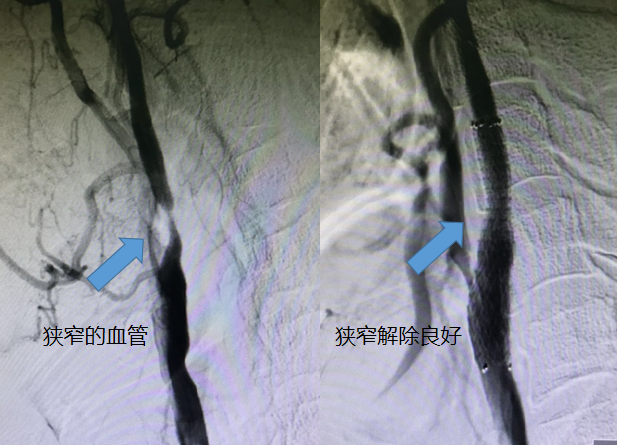

案例1

术前术后对比图

患者高先生,男,63岁,因头晕、言语不清90分钟入院,伴有右上肢活动麻木不适,查体:血压153/99mmHg,神志清,伴有构音障碍,左侧鼻唇沟稍变浅,口角右偏,双侧巴士征阴性,入院颅脑CT示:双侧基底节区腔隙性脑梗死。王司清主任查房,考虑患者仍处于后循环梗死急性期,有溶栓指征,立即启动溶栓流程,溶栓治疗1小时后,患者症状明显好转。积极治疗8天后,患者病情稳定。为进一步评估脑血管,行头颈部CTA检查示:右侧颈内动脉及右侧椎动脉重度狭窄。虽然右侧颈内动脉狭窄不是这一次的责任血管,仍有积极治疗的指征,遂于7月16日行局部麻醉下右侧颈内动脉支架置入血管成形术,再次造影显示狭窄解除良好,术毕,安返病房,监护2天后,病人未诉不适,现已出院。